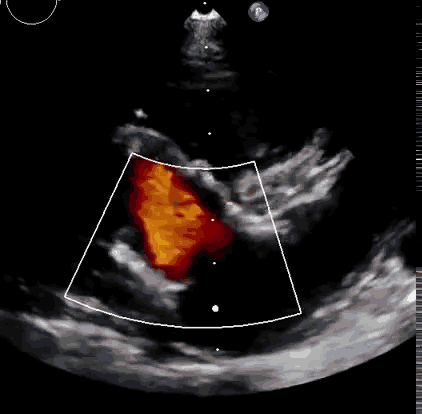

上海中山醫(yī)院葛均波院士、錢菊英院長、周達(dá)新教授、潘文志教授、潘翠珍教授、李偉教授共同完成此次臨床前研究。術(shù)后葛均波院士對Lux-Valve Plus的器械操作性能給予了高度評價,DSA和超聲影像也顯示出在本次研究中Lux-Valve Plus的安全性和有效性俱佳。

本次臨床前研究經(jīng)右側(cè)頸靜脈置入LuX-Valve Plus輸送系統(tǒng)可調(diào)彎鞘管,在DSA及超聲引導(dǎo)下將人工三尖瓣瓣膜植入到原有三尖瓣位置,利用獨特的錨定技術(shù)將人工瓣膜支架可靠固定在預(yù)定的位置。